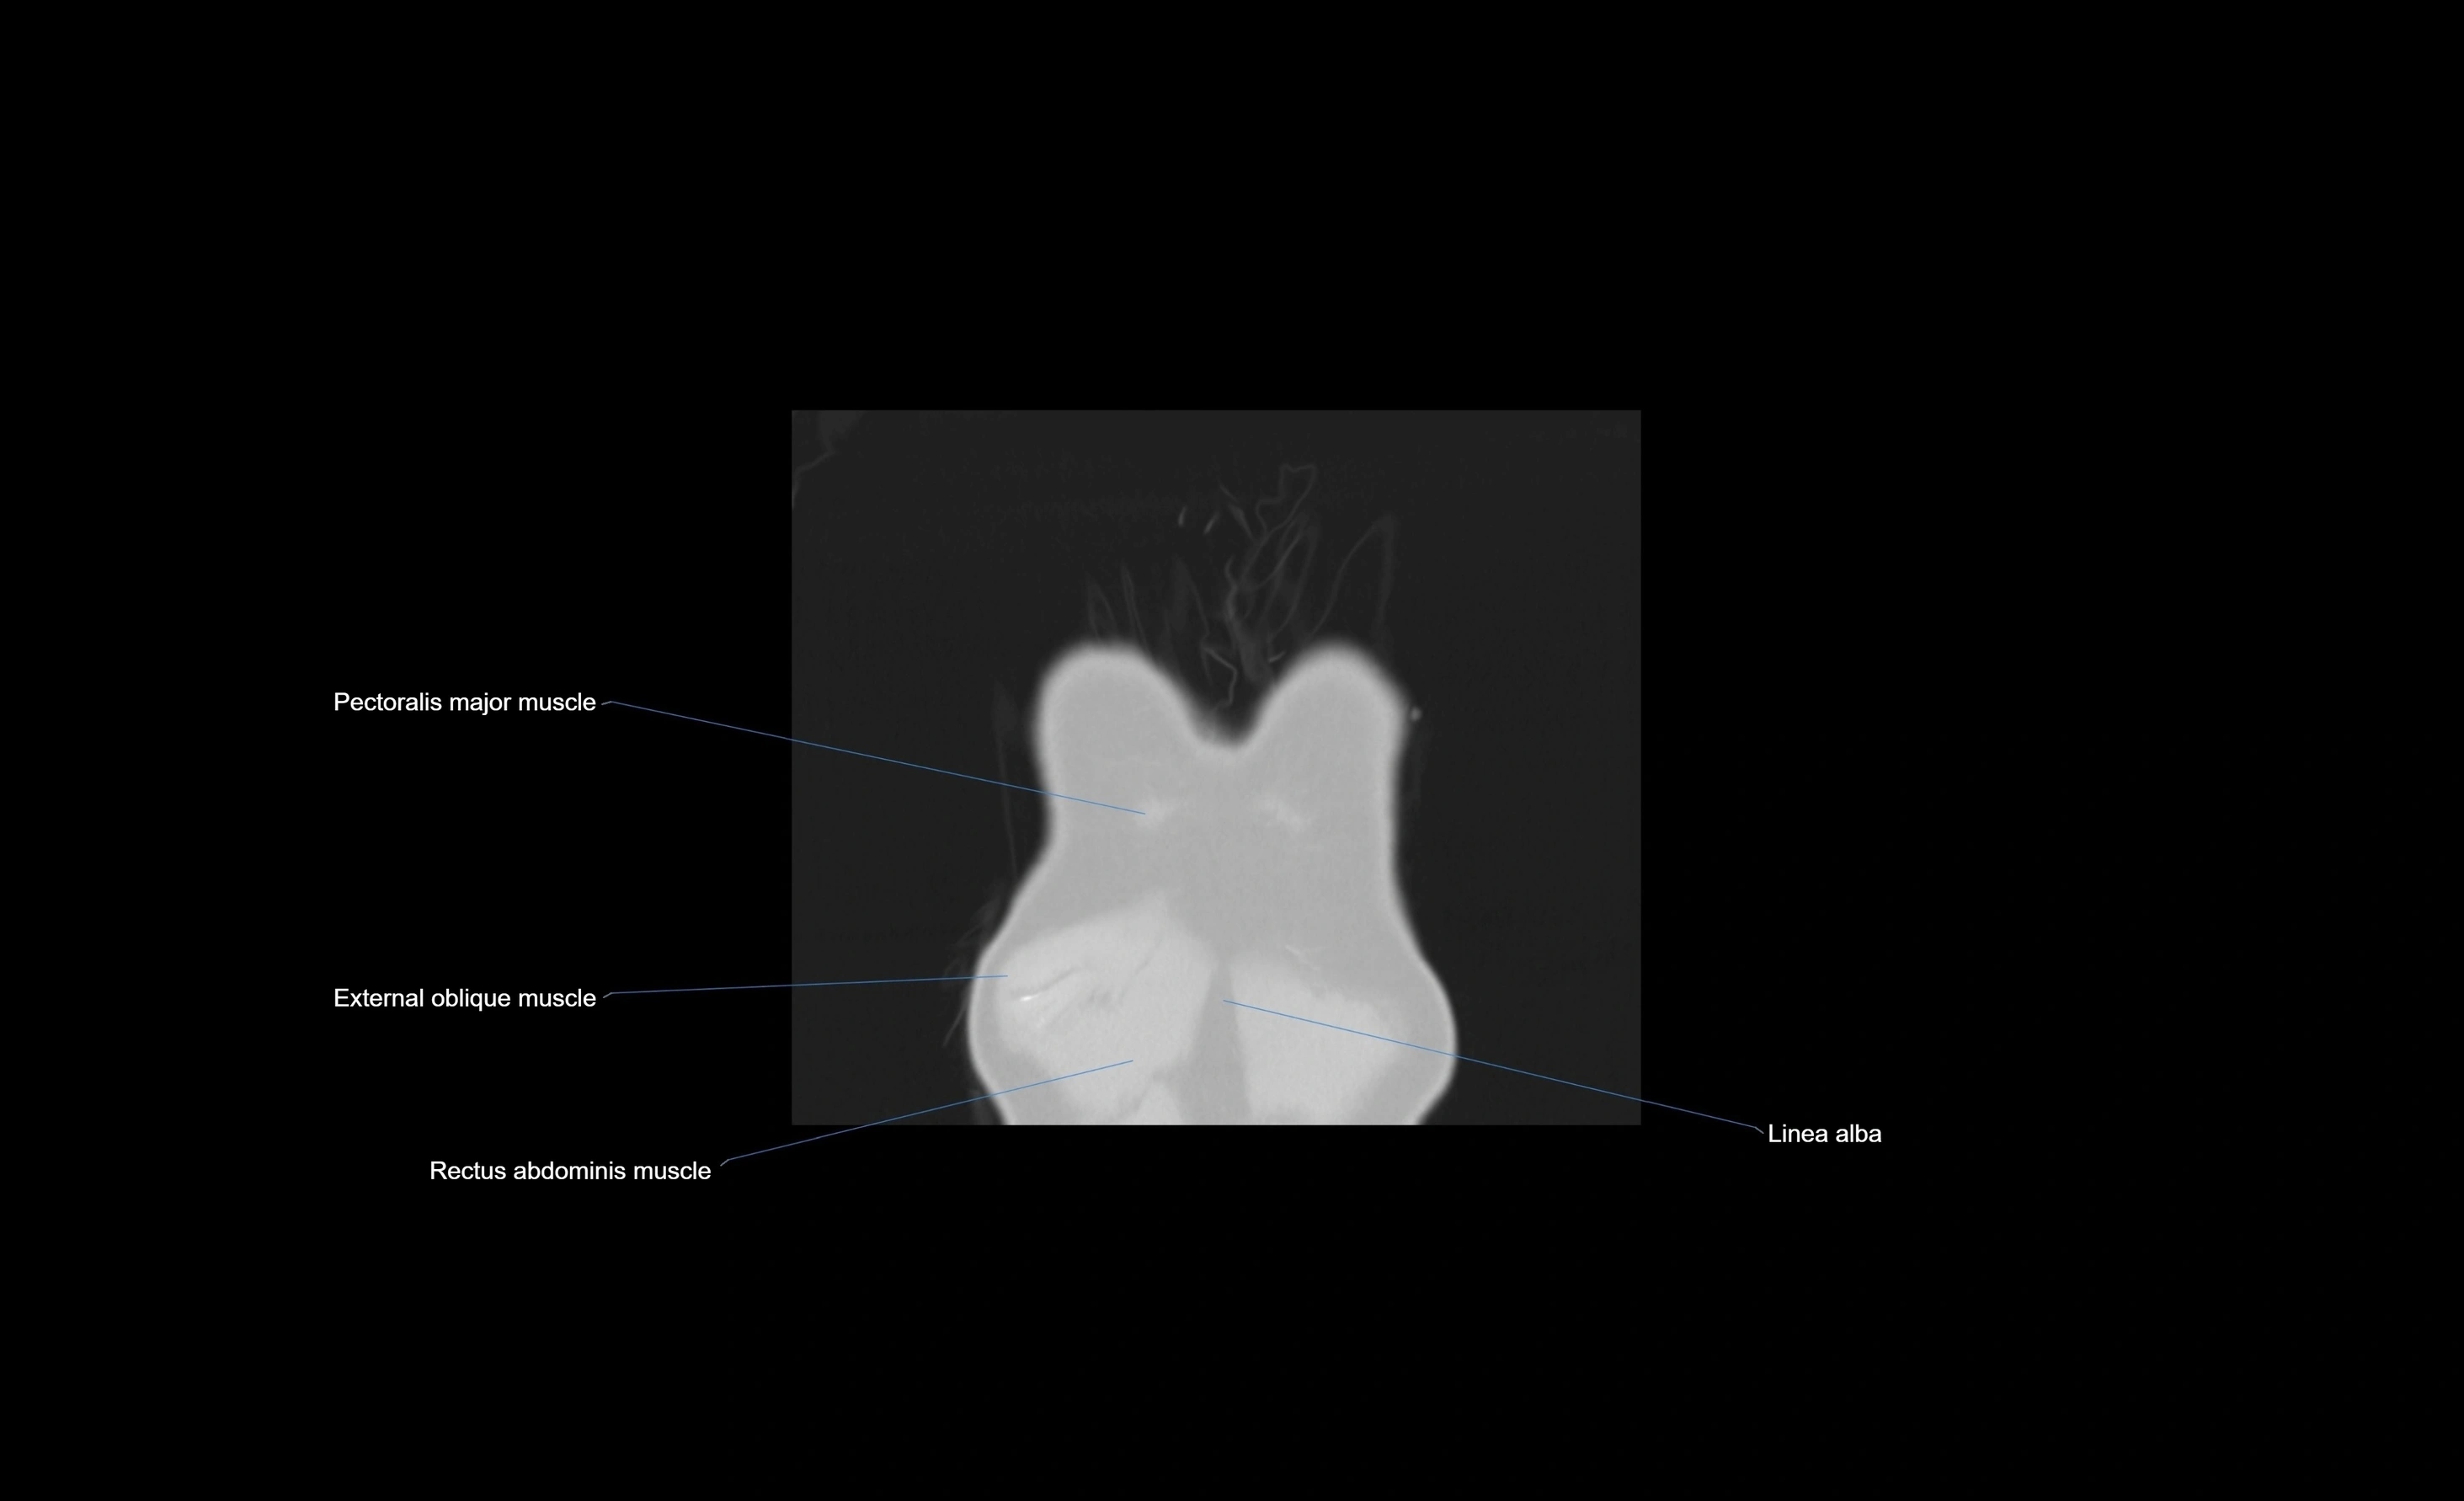

MRI images